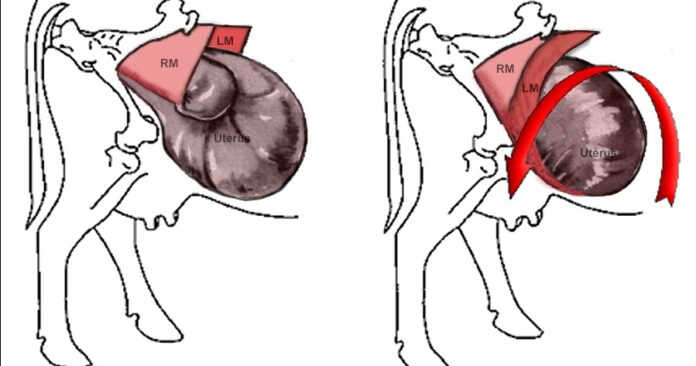

- Rolling of animal: Uterine torsion can be corrected by rolling the animal while uterus remain static. In case of mild degree of uterine torsion sudden rolling of animal might be effective. During sudden rolling rapid rotating body of the animal overtakes the slowly rotating gravid uterus which helps in repositioning of uterus. In Schaeffer’s method of uterine torsion correction the fetus is immobilized using a plank that is held in an inclined position on the animal’s abdomen after casting the dam in lateral recumbency to the side of torsion. Three individuals sustained pressure on the plank’s edge by standing on it while the animal was rolled to the other side. The modified Schaffer’s approach, which involves applying pressure from a person, was employed since the plank kept slipping over while the animal was being rolled. Three to four people placed pressure on the end of the plank that touched the ground by standing on it, while one person put pressure on the other end of the plank.